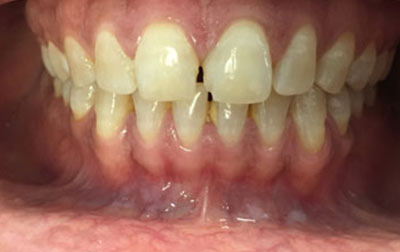

Invisalign: Invisalign is a revolutionary orthodontic approach using transparent, removable aligners. Virtually invisible, it provides discreet teeth straightening, ideal for those concerned about appearance. The aligners are easily removable, enabling hassle-free oral care and allowing consumption of any food. They offer greater comfort as they lack wires and brackets, with gradual adjustments for a comfortable experience.

Metal braces: Metal braces are the traditional orthodontic choice, using metal brackets and wires to achieve comprehensive teeth straightening. They excel in correcting complex alignment problems and are a reliable option. Metal braces are known for their durability and effectiveness, often resulting in shorter treatment times. Regular adjustments allow for precise control over tooth movement, making them a time-tested solution for achieving optimal alignment.